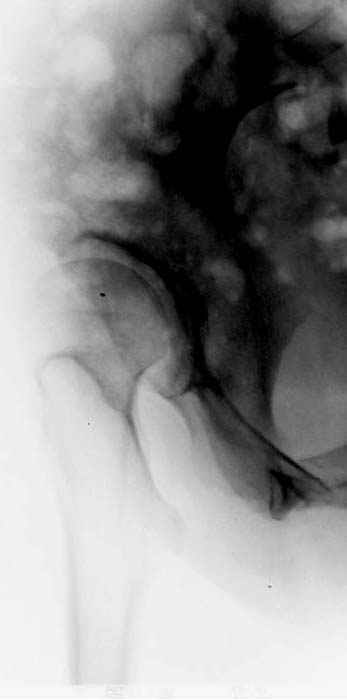

Рис.1 Трехмерная модель тазобедренного сустава с аналогом связки головки бедра. Заметно, что из торца головки выходит капроновый шнур, который с одной стороны прикрепляется к ножке бедренной части модели, а другой его конец, проходя через головку и прикрепляется к вертлужной части модели. Динамометр оказывается не нагруженным, так как аналог связки головки бедра замыкает подвижный узел модели во фронтальной плоскости.

Рис.2 Та же трехмерная модель тазобедренного сустава без аналога связки головки бедра. Пружина динамометра удерживает тазовую часть модели от опрокидывания, поддерживая стабильность так же, как отводящие мышцы обеспечивают ее в отсутствии связки головки бедра.